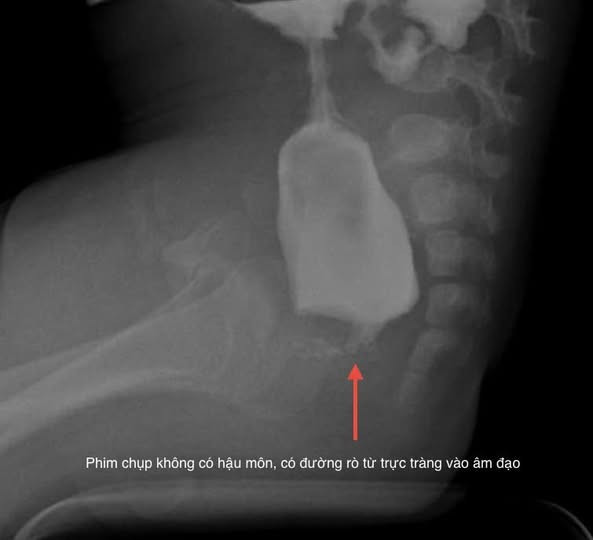

Mới đây, khoa Ngoại Tổng hợp vừa phẫu thuật nội soi cho một trẻ mắc dị tật không có hậu môn. Đây là một trường hợp rất đặc biệt, cháu Bùi Ngọc Kh. L địa chỉ tại An Lão, Hải Phòng, sau sinh đã phát hiện không có hậu môn, phân dò ra qua đường âm đạo.

Các bác sĩ tiếp nhận trẻ trong tình trạng suy dinh dưỡng, thiếu máu, có dị tật tiết niệu và rối loạn nhịp tim kèm theo, đại tràng sau quá trình ứ phân kéo dài bị giãn.

Sau khi được hội chẩn các chuyên khoa, mặc dù đại tràng giãn, phân bị ứ trong đại tràng nhiều phẫu thuật rất khó khăn, nhưng trẻ đã được phẫu thuật nội soi kết hợp đường sau trực tràng hạ đại tràng tạo hình hậu môn trong một lần mổ duy nhất.